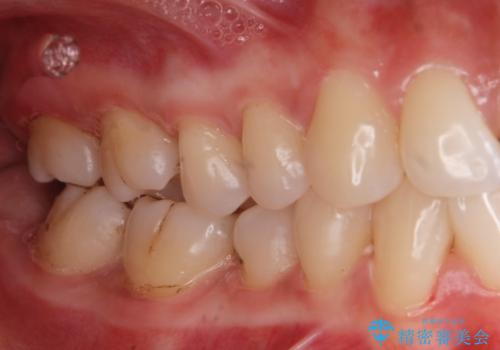

着色が気になる(エアフロー)

- 着色が気になるとの事で来院。

エアフローでしっかり着色を取り除きました。

着色が目立たなくなり大変満足して頂けました。